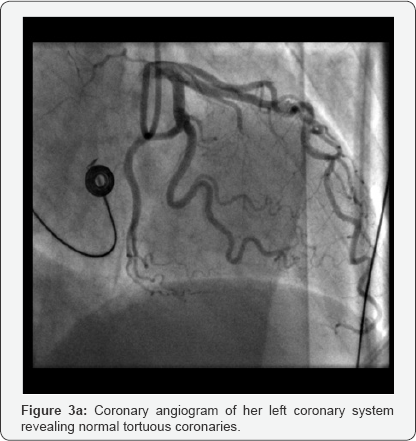

63-yrs old female who was known to have treated hypertension admitted to a local district general hospital with an index episode of witnessed seizures whilst travelling in a bus. She does have co-existing diagnosis of right occipital meningioma confirmed 18-months ago, for which she was awaiting radiotherapy. Also, she has a previous history of unprovoked spontaneous APE, 1-year ago, with anti-cardiolipin antibody positive and has successfully completed 6-months course of warfarin. On arrival, she was postictal with altered consciousness with agitation, therefore was intubated and ventilated towards urgent CT head. This confirmed increase in the size of her meningioma with surrounding areas of oedema; however, without any acute bleeding or features suggestive of hydrocephalus. Post- ictal ECG showed sinus rhythm with no significant abnormalities. Her bloods were unremarkable including normal electrolytes and glucose. After successful respiratory wean and complete neurological recovery she was stepped down to a general medical ward 72-hrs later. Later that night, whilst in the toilet developed sudden onset central chest pains and sweatiness. She was found to be hypotensive with systolic 100mm of Hg and hypoxic, despite clear lung fields. ECG revealed sinus bradycardia with ST elevation in antero-septal as well as inferior leads (Figure 1). She was given initial treatment for what clinically was thought to be a STEMI, including analgesics, antiplatelets (aspirin 300mg and ticagrelor 180mg) and transferred to local tertiary cardiac centre for further evaluation. Her urgent coronary angiogram performed trans-radially, showed typical hypertensive tortuous vessels; but relatively otherwise normal coronaries (co-dominant system) with TIM-3 flow distally (Figure 2). The left ventriculogram showed the presence of good systolic function. However, her blood gas analysis showed resting hypoxia with pO2 7.2KPa on room air and oxygen saturation of 86%. She had complete resolution of ST-elevation with development of incomplete RBBB morphology in her QRS complexes. Her bloods revealed high sensitive Troponin-T of 149ng/L [normal reference <15ng/L] and D-Dimer of 8.52mg/L Fibrinogen Equivalent, (FEU); [normal reference <0.5mg/L FEU]. Her urgent bedside echocardiogram showed anon-dilated left ventricle with good systolic function without any regional wall motion abnormalities. Her right heart was mildly dilated with reduction in RV free wall contractility as well as with mild tricuspid regurgitation; however, with no signs of chronic volume or pressure overload. There was no obvious thrombus seen within the right heart and no pericardial effusion seen. Her subsequent CT-pulmonary angiogram confirmed (Figure 3a & 3b) the presence of bilateral pulmonary embolism in her major pulmonary arteries without any evidence of infection or infarction or concurrent malignancies. The ultrasound venous Doppler of her legs revealed occluded right popliteal vein with thrombus. Subsequently following the neuro-surgical consult given her stable meningioma, she was started on anticoagulation with novel oral anticoagulant Rivaroxaban 15mg BD for 2 weeks and thereafter 20mg once daily planned for 6-months. Her subsequent out-patient bubble contrast echocardiography revealed intact inter-atrial septum without any presence of intracardiac shunts. Also, her cardiac MRI revealed no evidence of myocardial infarction or fibrosis or infiltration in her ventricles. Notably, there were no features of late gadolinium enhancementor myocardial oedema observed on T1 & T2-weighted imaging respectively. The right heart was nondilated with good systolic function and without any presence of intracardiac thrombus. Very importantly, investigations haven't identified the presence of occult malignancy as the underlying cause. As she remained clinically and haemodynamically well with normal saturations, she was discharged home and doing well on 3-month follow-up (Figure 4).